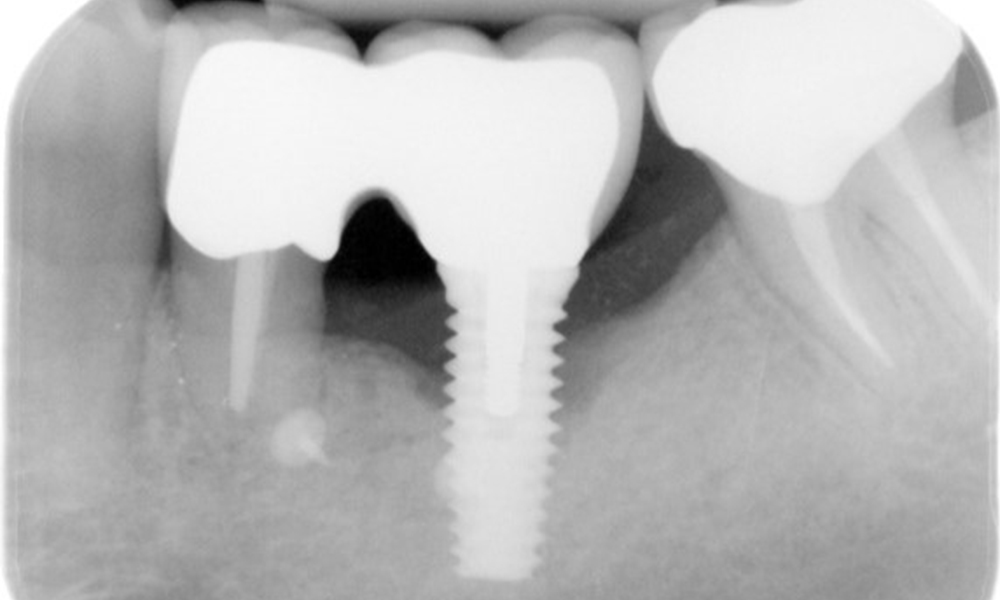

Ein 52-jähriger Patient stellt sich zur Präventionssitzung vor. Der Patient hat keine Allgemeinerkrankungen und nimmt keine Medikamente ein. Er hat verschiedene zahnärztliche Versorgungen und zudem zwei aktive kariöse Läsionen. Außerdem verfügt der Patient über vier Implantate (2., 3. und 4. Quadrant). Es zeigt sich eine parodontale Vorerkrankung (Stadium IV, Grad B). Derzeit herrschen stabile parodontale Verhältnisse, lediglich am Implantat regio 36 zeigen sich Sondierungstiefen (ST) von 5 mm. Zudem lässt sich eine Gingivitis feststellen.

Der Patient zeigt keine besonderen anamnestischen Risikofaktoren mit spezifischen zahnmedizinischen Auswirkungen. Daher ist der aus der Mundgesundheit ermittelte Bedarf maßgebend. Hierbei zeigt sich am Implantat im 3. Quadranten ST von 5 mm und im Röntgenbild eine Zunahme des Knochenverlustes. Der Patient hat zudem eine aktuell stabile parodontale Vorerkrankung und zwei aktive initialkariöse Läsionen.